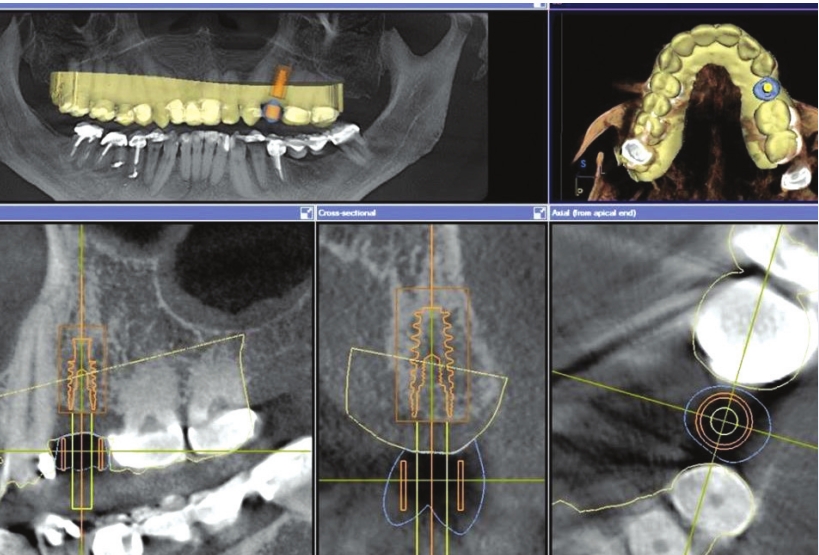

Step 3:

Then

the two scans are stitched together (virtually overlapped) to plan a

dental implant in the ideal position to support the future tooth already

designed. By stitching both images, one can see where the details of

the future crown lie and planning of the implant position is able to be

done confidently. This “perfect placement” assures we have the proper

loading forces (compression from chewing) on our future crown for the

implant and supporting bone structure. Here, we can also determine if an

extra bone augmentation procedure is necessary.